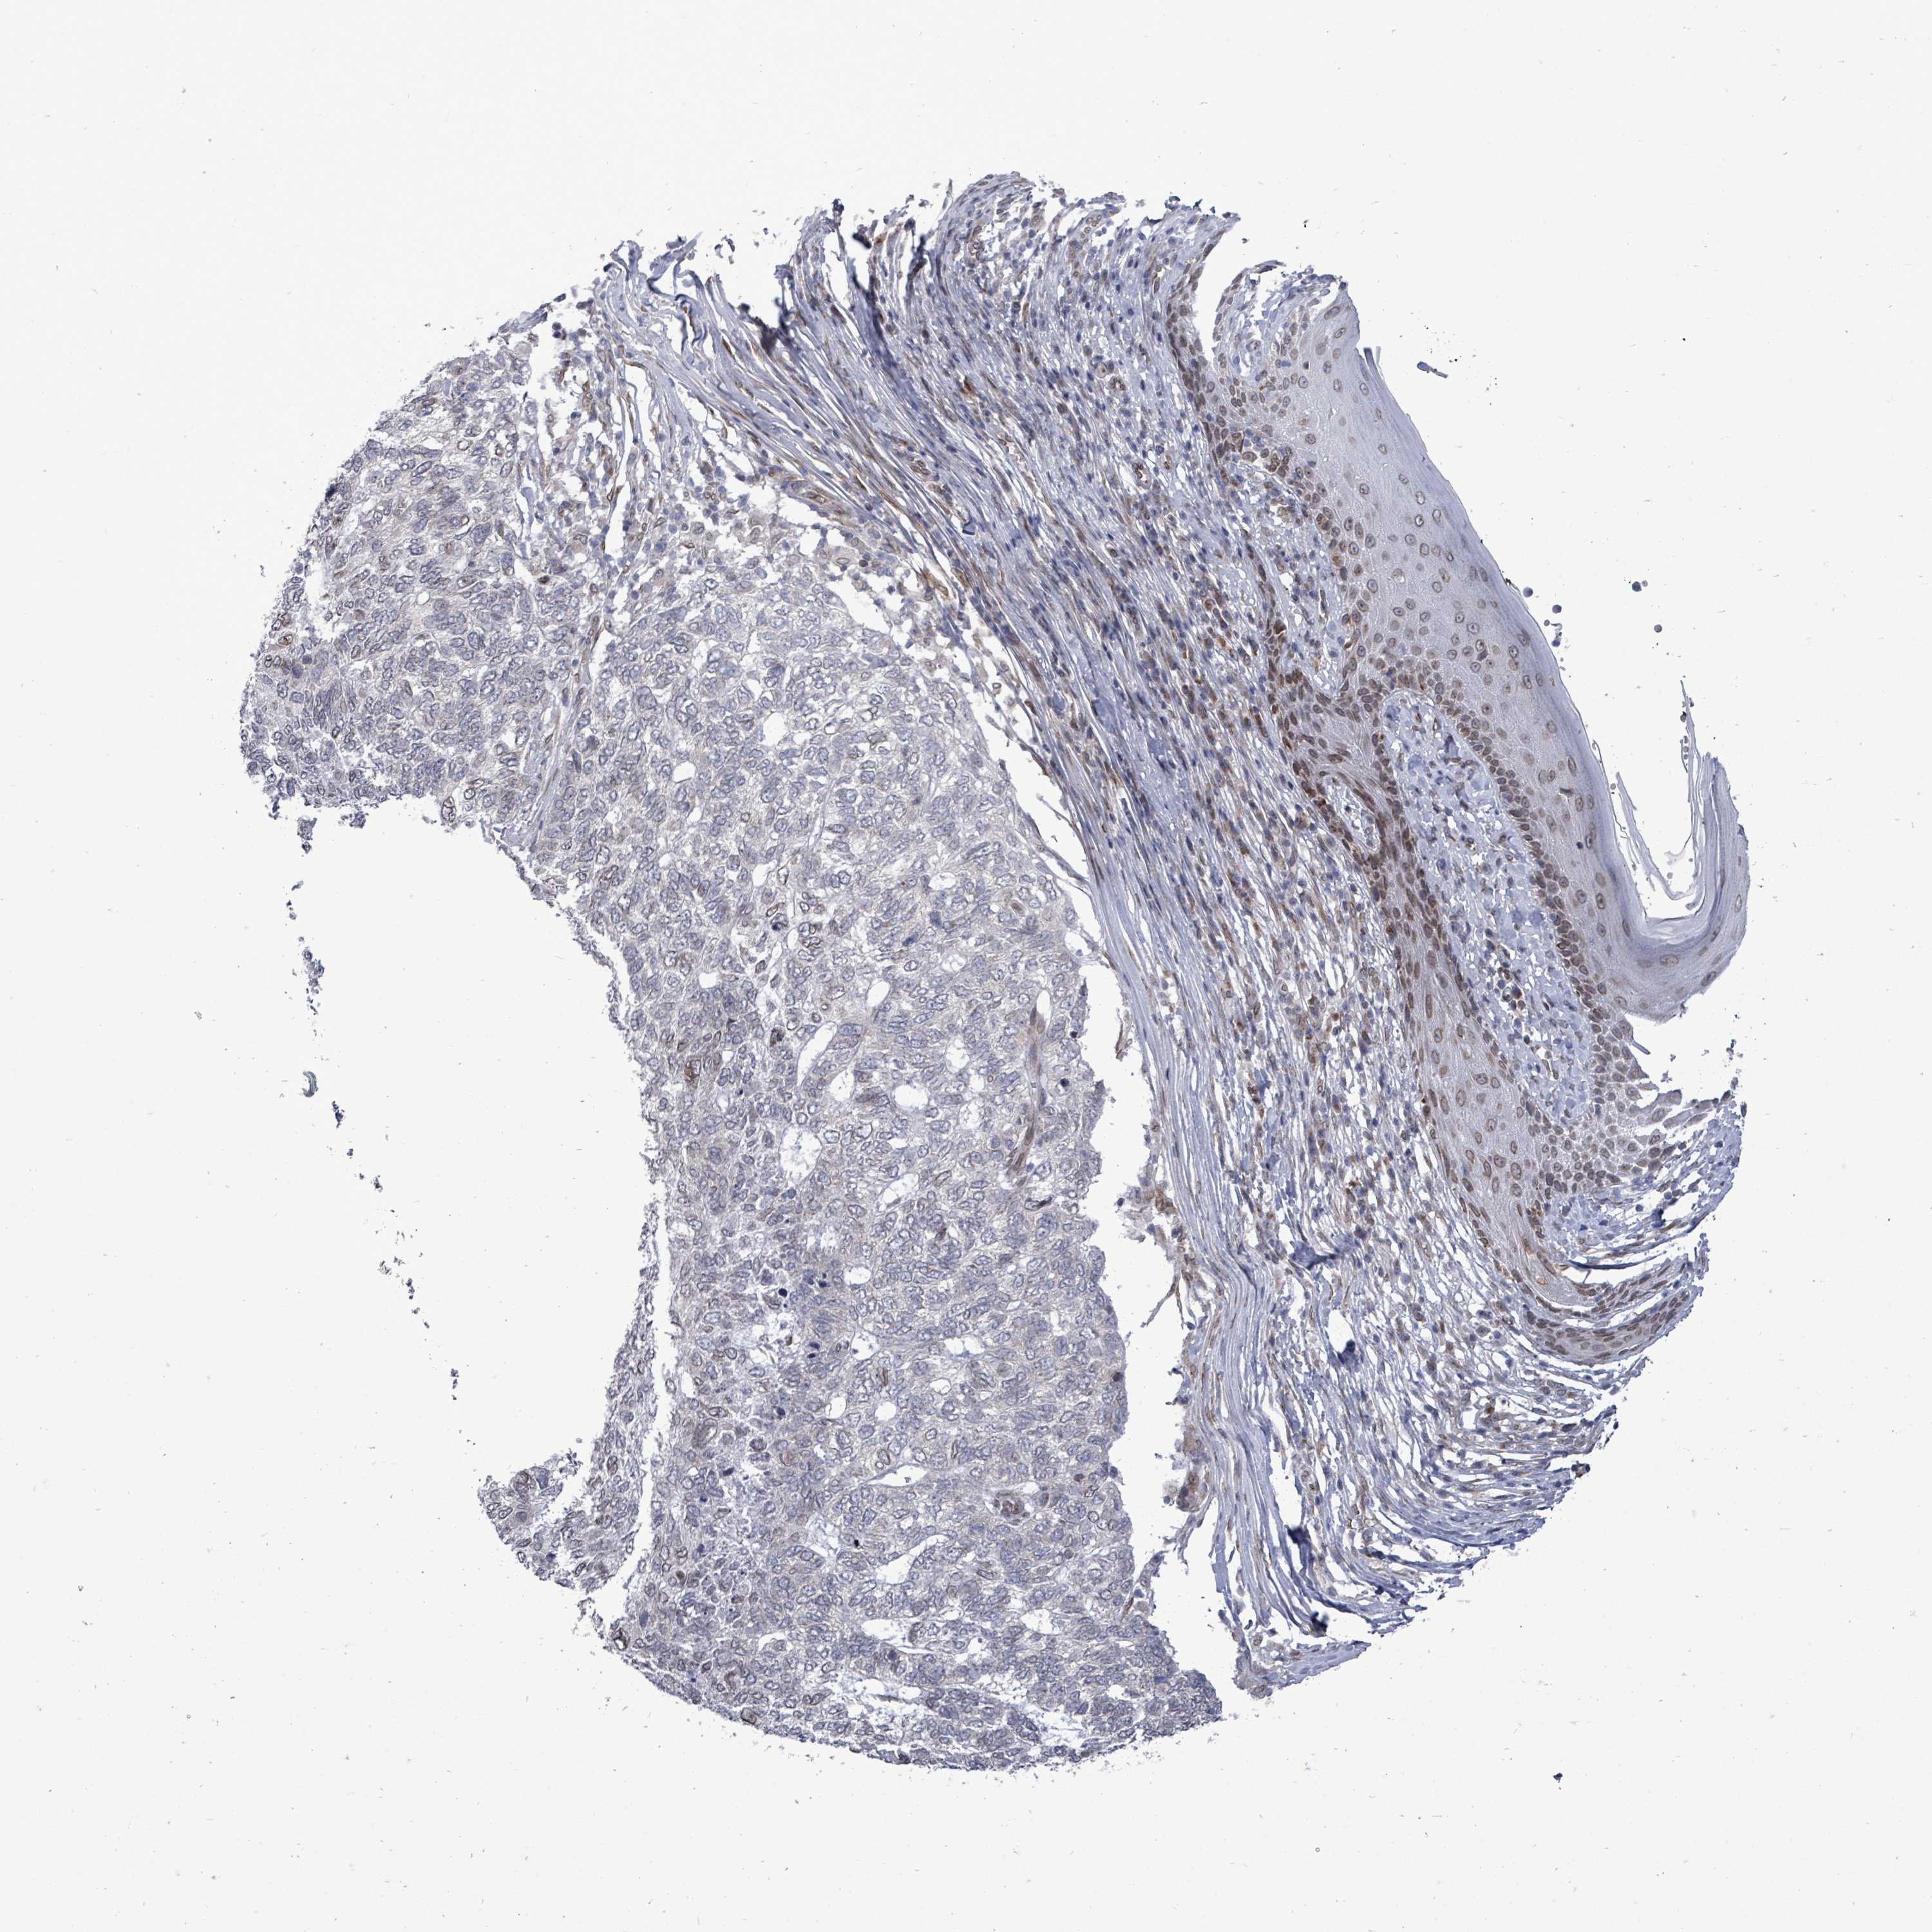

SKIN CANCER - Protein expressioni

A mouse-over function shows sample information and annotation data. Click on an image to view it in a full screen mode. Samples can be filtered based on level of antibody staining by selecting one or several of the following categories: high, medium, low and not detected. The assay and annotation is described here.

Antibody stainingi

Antibody staining in the annotated cell types in the current human tissue is reported as not detected, low, medium, or high, based on conventional immunohistochemistry profiling in selected tissues. This score is based on the combination of the staining intensity and fraction of stained cells.

Each image is clickable and will lead to virtual microscopy that enables deeper exploration of all samples and also displays staining intensity scores, fraction scores and subcellular localization as well as patient and tissue information for each sample.

Basal cell carcinoma

Squamous cell carcinoma, NOS

Squamous cell carcinoma, metastatic, NOS